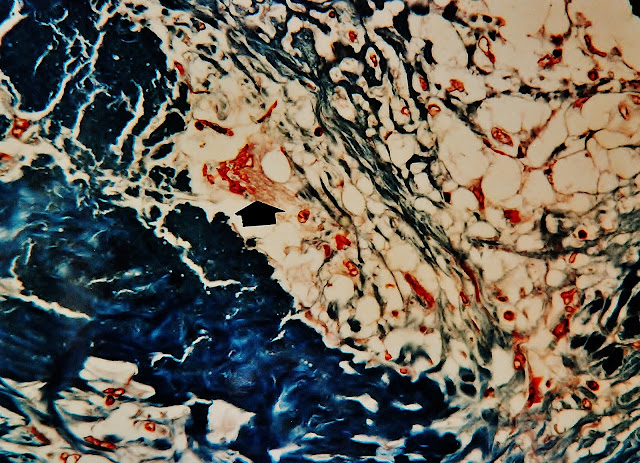

Fig. 3.-Detalle de la multicapa celular sustitutiva de la membrana quística germinativa, la cual ha desaparecido (Quiste inactivo). La flecha señalando una célula gigante multinucleada.Tricrómico de Masson. Prof. Garfia.A

Fig. 4.-Detalle para mostrar la formación de células gigantes multinucleadas (flecha), en el seno la cavidad quística, encargadas de la fagocitosis de la membrana germinativa. Tricrómico de Masson. Prof. Garfia.A